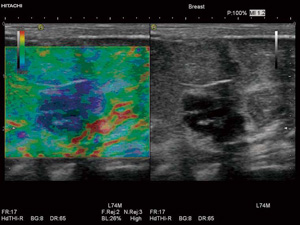

・Real-time Tissue Elastography

組織の硬さ情報を,画像としてリアルタイムに表示する組織弾性イメージング機能“Real-time Tissue Elastography(エラストグラフィ)”がさらに進化して搭載可能となりました。目的部位に探触子を軽く圧迫させるだけの簡単な操作で行えます。生体内の組織歪みから相対的な硬さを高速演算し,硬さ(変形)の程度をリアルタイムにカラー表示を行うことにより,周囲よりも硬い部分は青く表示されます。また,フリーズ後にROIの設定の変更が可能になり,さらに使いやすくなりました。

Real-time Tissue Elastography